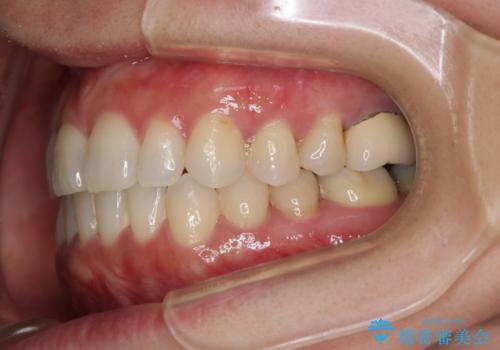

- 前歯のがたつきと反対咬合を主訴に来院されました。

インビザライン・クリンチェック(歯のシミュレーション)を行い、

インビザラインライトで治せる範囲であることを確認し治療を開始することになりました。

今回はクリンチェックを作成したのちに、枚数が少なくても可能であることが判明したためインビザラインライトでの治療を行いました。

最初はインビザラインモデレートパッケージの予定で契約をされていたので、金額も10万円以上安くなり仕上がりも満足頂きました。